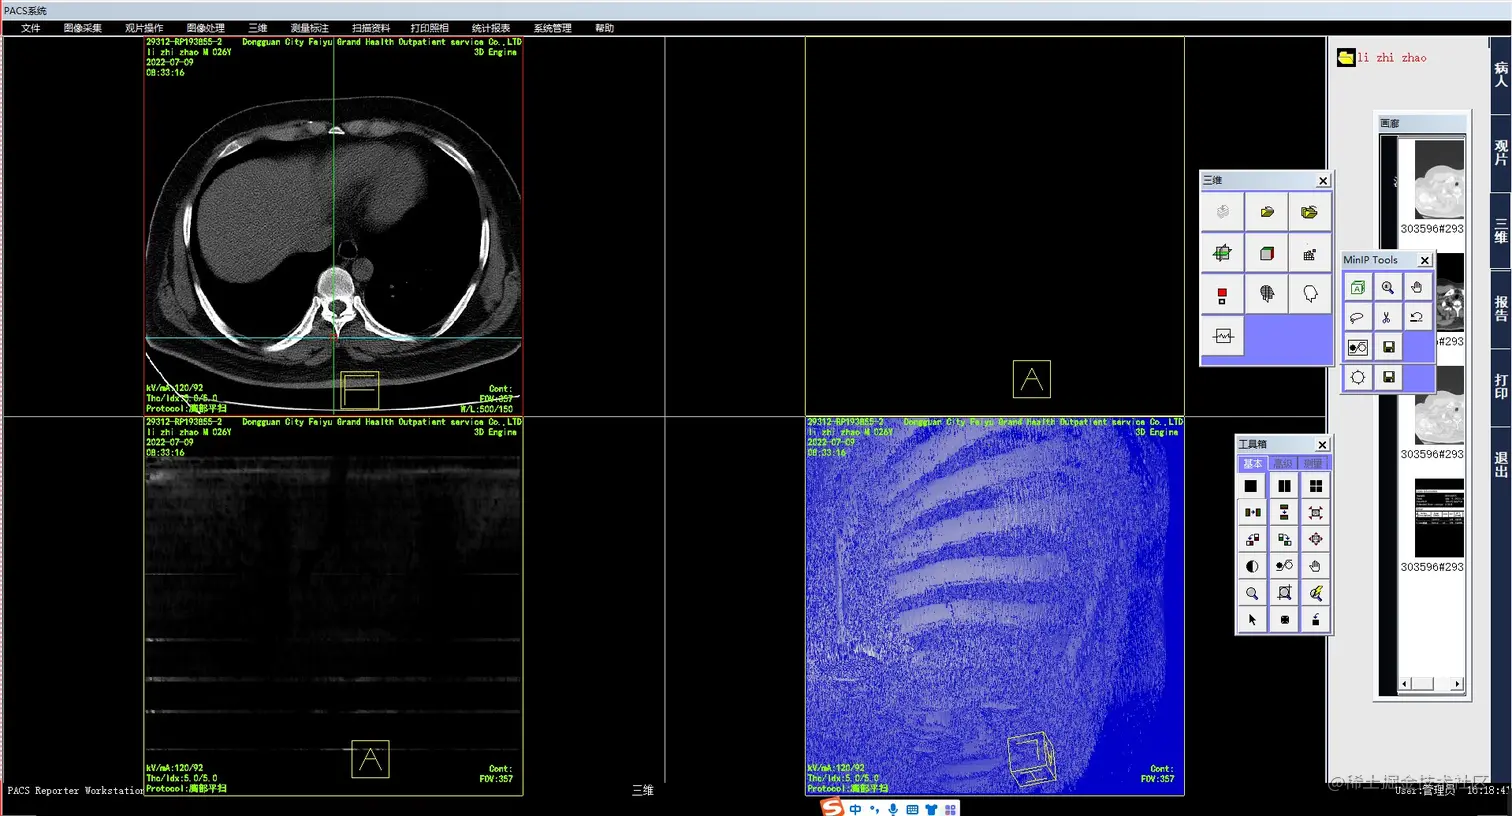

医院影像PACS系统是一种基于计算机技术的影像信息管理系统,旨在提高医院影像信息的质量和管理效率,满足医院影像科室的日常工作需要。本文将详细介绍医院影像PACS系统的各项功能,包括检查预约、病人信息登记、计算机阅片、电子报告书写、胶片打印、数据备份等一系列满足影像科室日常工作的功能。

3.计算机阅片:影像医生可以通过系统的计算机阅片功能,快速、方便地浏览患者的影像资料,并进行快速的诊断和处理。系统将自动生成电子报告,并将报告发送给相应的医生和护士。